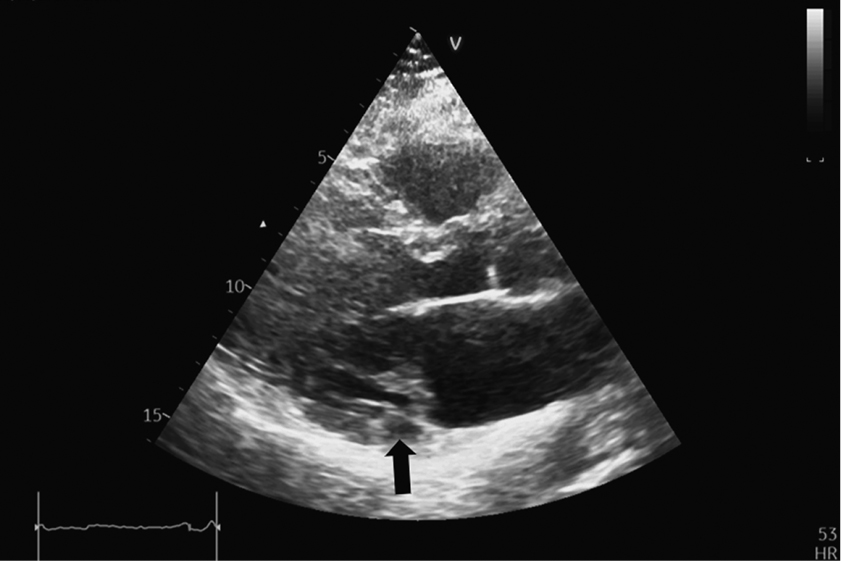

EchoCG was performed using modern technologies of three-dimensional image reconstruction and Mitral Valve Quantification model on Vivid-9 ultrasound device. The results showed that mitral regurgitation was mild [16]. The effective regurgitation orifice area was 0.18 cm2, and the regurgitation volume was 20 mL. Both mitral valve leaflets were myxomatous, thickened, and prolapsed up to 8 mm into the LA cavity (Fig. 1–3). The prolapse was polysegmental (Fig. 4). Signs of MAD (absence of myocardial tissue up to 9 mm under the posterior mitral valve leaflet) were revealed (Fig. 1, 2).

Fig. 1. Parasternal long-axis view of the left ventricle. Systole. White arrows indicate elongated and thickened mitral valve leaflets prolapsing into the left atrial cavity. The black arrow indicates the disjunction area